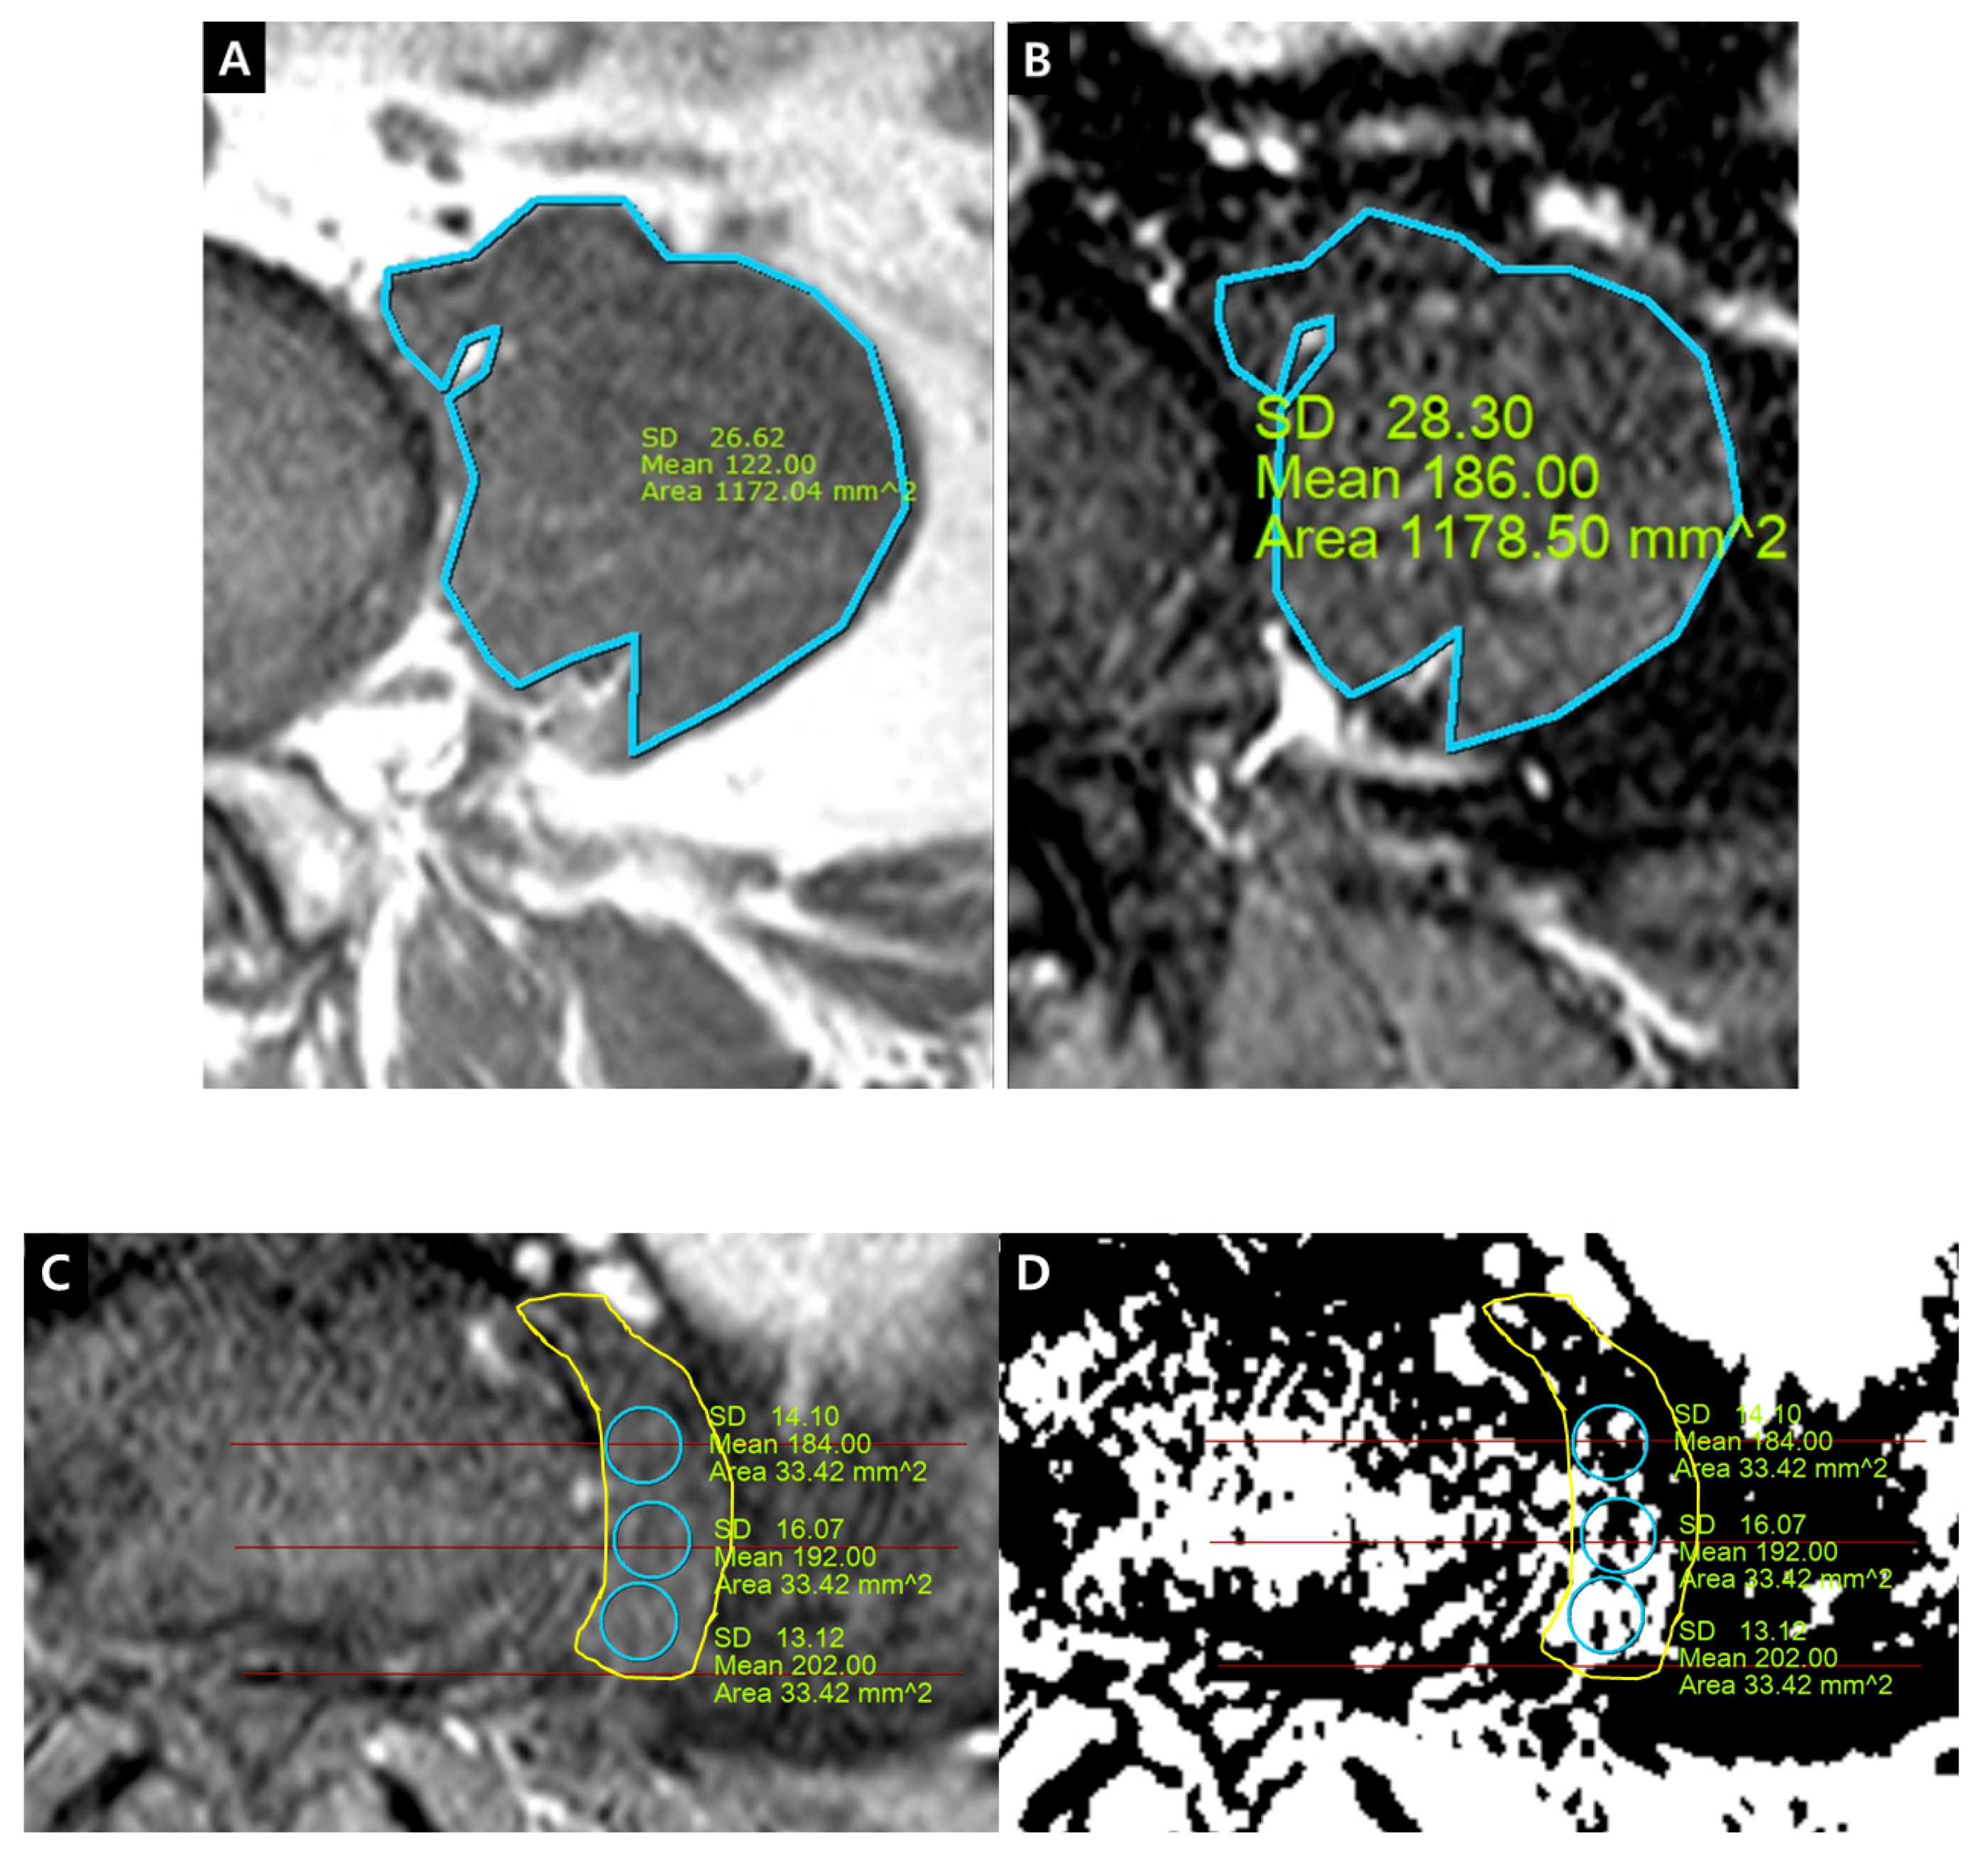

Figure 5. Whole rootlets IRCE (WR-IRCE) on L4–5 as a control. (A) T2-weighted axial image; (B) fat-suppressed enhanced T1-weighted axial image. SD—standard deviation

Figure 6. (A) dural cross sectional area (DCSA) on T2-weighted axial image; (B) whole rootlets IRCE (WR-IRCE, yellow color) and maximal spot rootlet IRCE (MS-IRCE, red color) on fat-suppressed enhanced T1-weighted axial image among signal intensities of manually-defined whole rootlets and each rootlet.

The quantification of IRCE was evaluated by the ratio (%) of signal intensities between the cauda equina and psoas muscle on the same axial enhanced image. The signal intensity of rootlets was measured within the manually defined region of interests (ROIs) along the boundary of the white signal by a digitizer, Maroview software (Infinitt Healthcare Co., Seoul, Korea). To define an exact margin, intrathecal rootlets were marked on the same T2-weighted axial image. The adjustment of the gray scale (window level) was necessary for the discrimination between the rootlets and cerebrospinal fluid. Manual ROI analysis was performed by superimposing previously acquired ROI on the enhanced fat-suppressed T1-weighted image (Figure 5). Two methods were composed of whole rootlets IRCE (WR-IRCE) and maximal spot rootlet IRCE (MS-IRCE) at the most stenotic level (Figure 6). WR-IRCE was obtained by recording the mean signal intensities of all outlined intrathecal rootlets. MS-IRCE was defined as the maximum value in circular ROIs (0.18 mm2) among intrathecal rootlets. In some patients, the large radiculomedullary veins showed strikingly higher signal intensities (>315) than those of other rootlets. These high signals were excluded in the subsequent measurements. The measurement of WR-IRCE and MS-IRCE on the L3–4 and L4–5 levels, respectively, were also performed in the asymptomatic control group to find a difference between such levels. The signal intensity measurement of the psoas muscle was performed within manually defined ROIs (Psoas1), which were delineated along the margin of the unilateral psoas muscle on the same enhanced axial images. In addition, circular ROIs (33.42 mm2, Psoas2) were designated within the medial portion of the psoas muscle corresponding to a mid to posterior disc space to avoid field inhomogeneity (Figure 7). Using these signal intensities, four rootlet-to-psoas ratios were defined (MS/P1 = MS-IRCE/Psoas1*100, WR/P1 = WR-IRCE/Psoas1*100, MS/P2 = MS-IRCE/Psoas2*100, WR/P2 = WR-IRCE/Psoas2*100). Those parameters were analyzed to identify the best possible candidate to stratify patients with lumbar central stenosis.